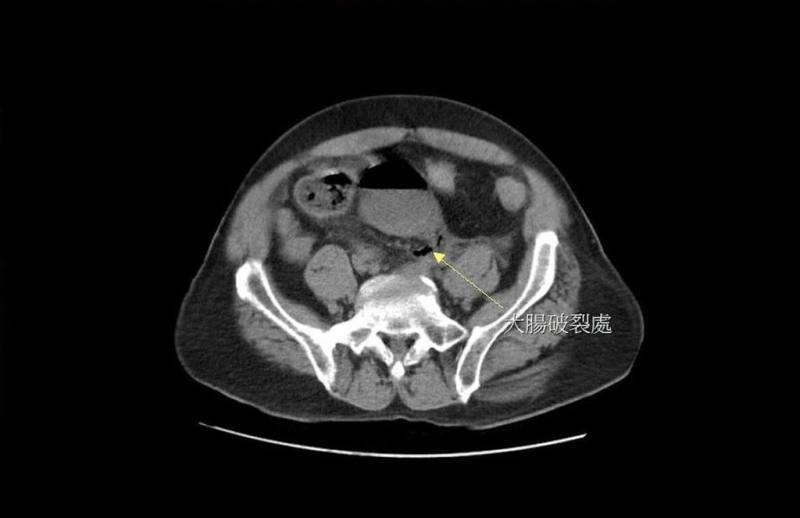

苗栗縣大千綜合醫院27日分享案例,一名男子長期便秘經常自行灌腸,因力道過猛造成直腸破裂,糞水隨破洞流進腹腔,引發嚴重腹膜炎。(大千醫院提供)

大千醫院指出,黃男日前又因連續3天無法解便而自行灌腸,發現沒有效果,於是改用更長的管子,把瀉藥送入直腸深處灌腸,突然引發劇痛,被家人緊急送至醫院急診,經電腦斷層掃描後發現,男子直腸上端處有巨大破洞,糞水隨著破洞流進腹腔,引發嚴重腹膜炎。

大千醫院外科部主任馮啟彥緊急進行腹腔鏡手術,術中發現破洞位於直腸上端靠近乙狀結腸的轉彎處,直徑約2公分,研判應是太用力灌腸造成的腸道破裂,也讓大量的宿便流進腹腔,才會引發嚴重的腹膜炎。所幸黃男術後順利康復,但也嚇得直呼「再也不敢自己隨意灌腸了」。